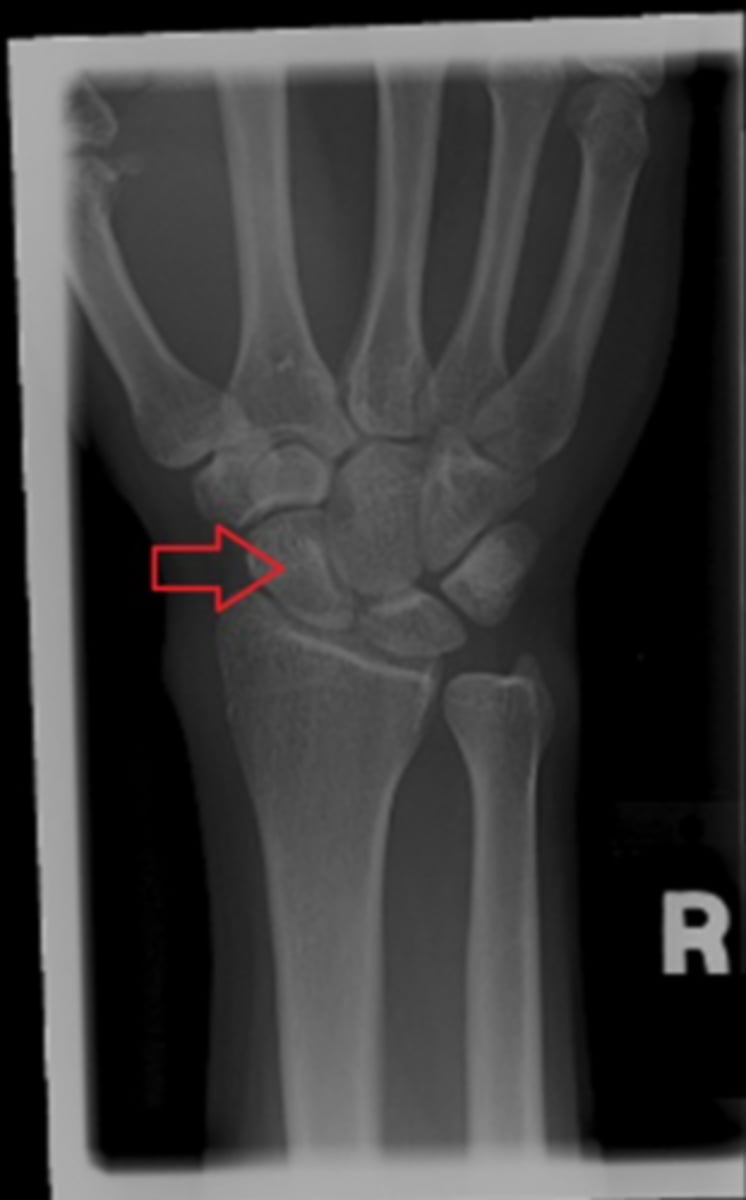

c. scaphoid

on the given wrist image, the red arrow point to the...?

a. capitate

b. lunate

d. triquetrum